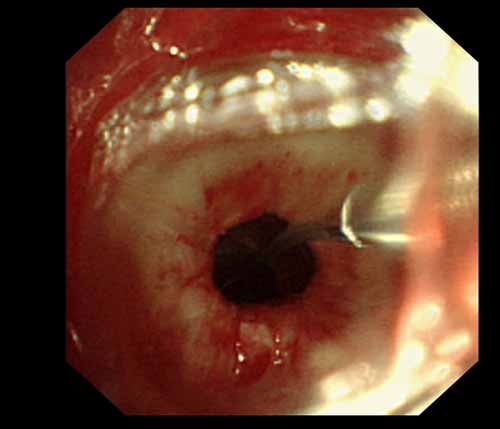

患者李某某,女,45歲,因氣管插管咳嗽、喘憋10天入院。頸部CT檢查示聲門下約20mm處氣管明顯狹窄,狹窄段長約26mm,最窄處直徑約4.4mm。支氣管鏡檢查見聲門下約2cm氣管呈漏斗狀縮窄,直徑約4-5mm,支氣管鏡無法通過。經科室討論,決定行電子支氣管鏡下氣管球囊擴張治療。與患者及家屬充分溝通并經三方見證談話簽署知情同意書后,在患者持續吸氧、局麻下,科主任于世倫主任醫師帶領治療小組為患者實行電子支氣管鏡下氣管球囊擴張術。手術過程順利,出血量很少,術后患者呼吸困難癥狀即可明顯緩解。10天后行二次擴張,患者日常活動無明顯喘憋,二次術后5天出院。

術中球囊擴張